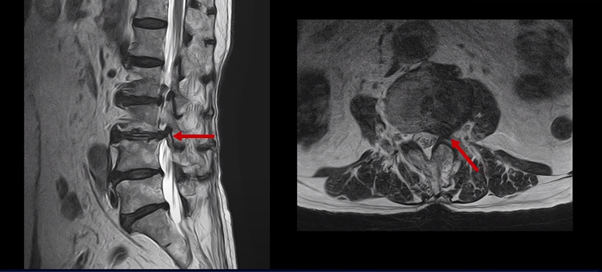

이 두 마디가 왼쪽 증상, 특히 허벅지 통증을 일으키는 원인으로 보입니다. 이렇게 여러 마디가 안 좋을수록, 또 고령일수록 수술하기가 더 까다로워지는데 또 큰 문제는 이 환자분은 근감소증이 심하게 진행된 상태로, 여기 MRI에서 보시다시피 허리 하부의 기립근 근육이 전부 지방으로 변해버려 근육 자체가 거의 없는 상태인 것입니다.

근육이 없는 근감소증 환자는 척추수술 후 예후가 더 안 좋은 것으로 알려져 있기 때문에 상담하신 정형외과에서도 수술 권유를 안 한 것으로 보입니다.

그런데 한편으로 다행인 것은 이분 척추는 여러 마디 다 문제이기는 하지만 저희가 보는 환자 중에서 신경 구멍이 아예 보이지 않을 정도로 막힌 협착증 환자분이나 신경 구멍을 거의 다 막을 정도로 심하게 디스크가 파열된 환자분들에 비해서는 신경의 눌림 정도는 많이 심하시지는 않은 상태셨습니다. 이런 상태라면 더 빠른 호전을 기대해볼 수 있을까요?